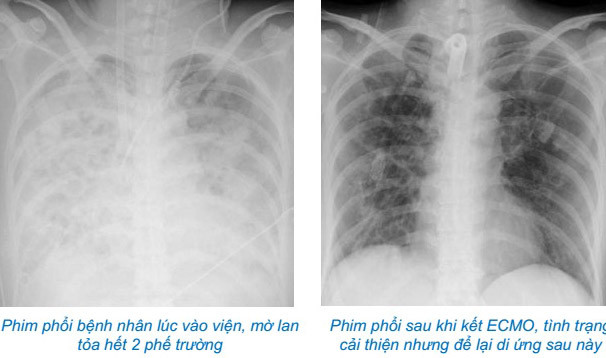

Bác sĩ Nguyễn Bá Cường, Trung tâm Hồi sức tích cực (Bệnh viện Bạch Mai) cho biết, khi nhập viện, tình trạng bệnh nhân rất nặng, sốt cao liên tục, sốc nhiễm khuẩn nặng, oxy máu giảm rất thấp, X-quang phổi mờ trắng xóa cả 2 bên phế trường, test nhanh Cúm B dương tính.

Hình ảnh phim phổi của bệnh nhân. Ảnh: BVCC

Bệnh nhân sau đó không đáp ứng với điều trị hồi sức, phải tiến hành can thiệp ECMO cấp cứu. Trong quá trình 37 ngày chạy ECMO, gần 50 ngày thở máy với oxy liều cao, do suy giảm khả năng đề kháng, bệnh nhân rất dễ nhạy cảm với các vi sinh vật trong bệnh viện và phải điều trị nhiều đợt kháng sinh, kháng nấm. Các bác sĩ đã phải nhiều lần hội chẩn trong khoa và liên khoa để kịp thời đưa ra phác đồ điều trị thích hợp cho từng diễn biến của bệnh.

Sau hơn 2 tháng nằm điều trị hồi sức tích cực, ngày 3/1, bệnh nhân được ra viện. Tuy nhiên các tổn thương phổi sau đó có thể sẽ còn tồn tại và cần phải theo dõi trong thời gian dài.